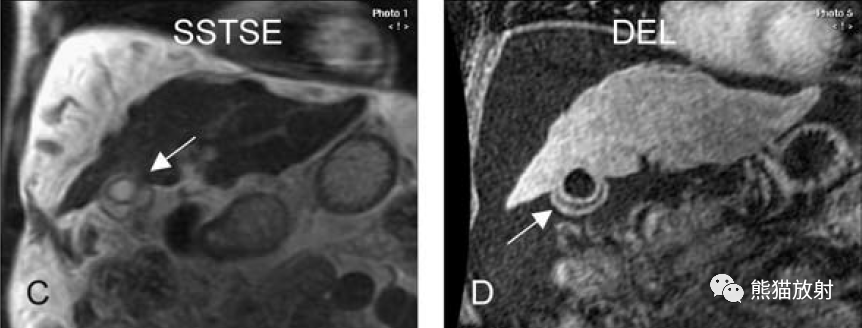

膽囊癌。A~D圖:上方層面,表現(xiàn)如上所述,形成腫物侵及肝臟。E、F圖:下方層面示膽囊壁不規(guī)則增厚,明顯不均質(zhì)強(qiáng)化。

膽囊壁增厚(并肝硬化、門(mén)脈高壓、腹水)。T2WI顯示膽囊壁因水腫而光滑均勻增厚,增強(qiáng)延遲期顯示強(qiáng)化的膽囊壁(內(nèi)外兩層:粘膜層和漿膜層),薄而清晰光滑。

T2壓脂(T2 fatsat):膽囊窩內(nèi)膽囊癌病變較肝臟為高信號(hào),病變頂部向肝內(nèi)擴(kuò)展;

增強(qiáng)動(dòng)脈期(ART):不均質(zhì)強(qiáng)化;

延遲期(DEL):部分廓清,部分持續(xù)強(qiáng)化。